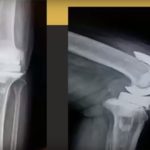

Proximal humerus fractures - Fix or replace?